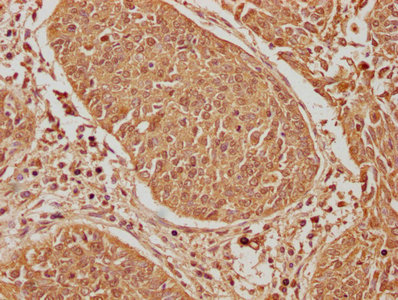

IHC image of CSB-PA007511LA01HU diluted at 1:600 and staining in paraffin-embedded human cervical cancer performed on a Leica BondTM system. After dewaxing and hydration, antigen retrieval was mediated by high pressure in a citrate buffer (pH 6.0). Section was blocked with 10% normal goat serum 30min at RT. Then primary antibody (1% BSA) was incubated at 4°C overnight. The primary is detected by a biotinylated secondary antibody and visualized using an HRP conjugated SP system.